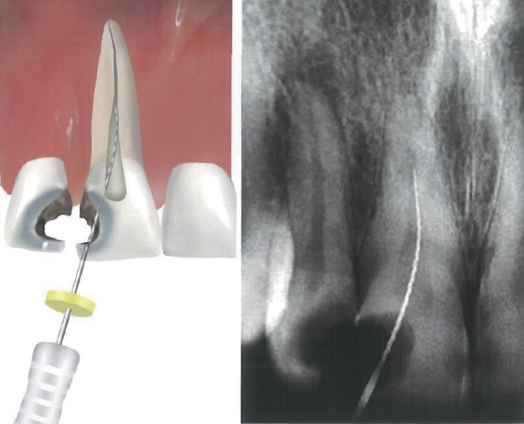

开髓洞形

“适当”开髓洞形的定义在过去几年中经历了一些变化。一个完整的开髓洞形仍应让操作者能够看见所有的根管口,并能够引导器械进入根管,直达根尖或到达第一弯曲点。洞壁的干扰或者根管冠1/3未去除的根管口牙本质三角会因为增加弯曲的数量和程度(医源性S弯曲)而增加根管预备中施加在器械上的压力,这会导致器械疲劳(图1~图3)。相反,如果开髓洞形超出了髓室的范围,也会妨碍根管锉进入根管,并导致根管锉的尖端触壁发生弯曲。

根管马达怎么修根管内器械分离的影响因素_https://www.jmylbn.com_新闻资讯_第2张

1  过小开髓孔导致的下颌磨牙近中根管中器械分离。可见髓室顶(短箭头)和未充分磨除的根管口牙本质三角(长箭头),这些都妨碍了根管冠1/3处直线通路的建立

根管马达怎么修根管内器械分离的影响因素_https://www.jmylbn.com_新闻资讯_第3张

2  在近中或远中龋损基础上建立的无便利形的开髓孔,器械无法直线通路到达根尖,最终导致一系列医源性失误

根管马达怎么修根管内器械分离的影响因素_https://www.jmylbn.com_新闻资讯_第4张

3  术前片(左上1~2图)可见两颗上颌中切牙根管内都存在分离器械,很可能是因为基于近远中病损建立的开髓孔,无便利形所致。规范开髓后,分离器械被取出并完成了根管治疗。右上图和左下图为3个月和12个月的复诊片显示病变逐渐愈合